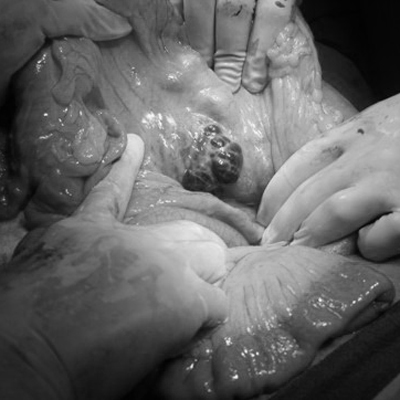

Ciddi komplikasyonlar

Pankreatit ile ilişkili şiddetli ağrı, normal olarak ince barsaklarda aktive olan besinleri sindiren enzimlerin pankreas içinde kalması ve bunun yerine pankreasa saldırmasıdır. Pankreatit ayrıca, pankreasın vücudun glikoz (şeker) seviyelerini düzenlemek için gerekli olan insülini serbest bırakma yeteneğini de etkiler. Pankreas enzimlerinin pankreas dokusunu harap etmesine ilaveten etrafta bulunan damarlarda bazen zedelenmeler görülebilir. Pankreas kisti (psödokist), pankreas etrafında apseler, akciğer başta olmak üzere diğer organlarda yetmezlikler ve hasarlanmalar olabilir. Akut pankreatitis eğer şiddetli ise bazen şeker hastalığı oluşturabilir.